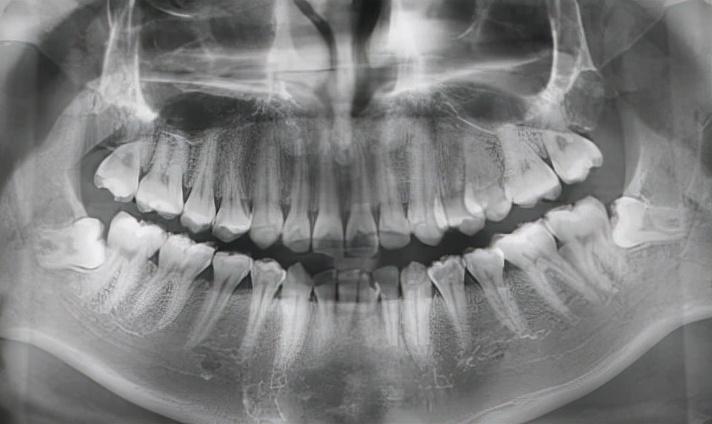

③拔除斜長、橫長或埋在骨頭里的下頜智齒,難度系數(shù):★★★★

其實,這些就是我們俗稱的阻生牙。

這一類智齒比較難拔,基本上都是微創(chuàng)手術(shù)了,但也需要切開牙齦操作,手術(shù)難度還是不低的。因此價格相比前兩種手術(shù)會高一些。

下頜智齒水平生長

當然,還有其他更加奇奇怪怪的pose……

各類“不聽話的”下頜智齒